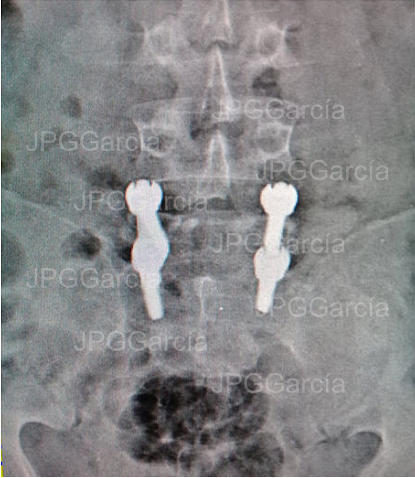

Instrumentación Lumbar Posterior por Espondilolistesis

Degenerativa (vistas lateral y anteroposterior)

Instrumentación Lumbar

Posterior por Espondilolistesis

Degenerativa (vistas lateral y

anteroposterior)